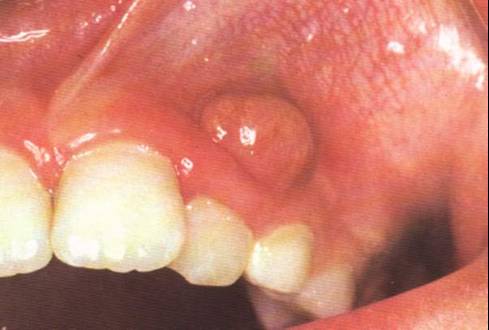

尖周脓肿或慢性牙槽脓肿:医生介绍,尖周脓肿或慢性牙槽脓肿是局限于尖周区的慢性化脓性炎症。尖周脓肿可穿过牙槽骨及粘膜形成牙龈窦道,或穿通皮肤形成皮肤窦道。一般无自觉症状,叩诊时有轻微疼痛,有反复肿胀史,X线片显示周有边界不整齐的弥散性稀疏区。